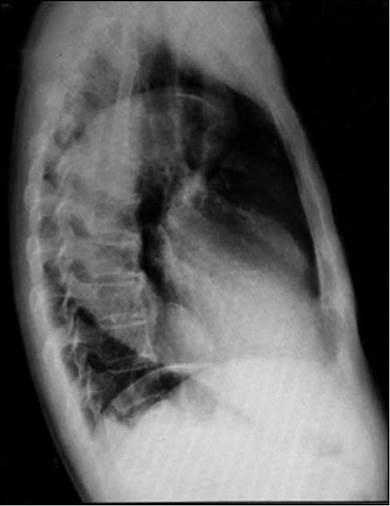

Paciente masculino de 85 años, con cuadro de 12 horas de evolución consistente en dolor torácico opresivo, intensidad moderada, no irradiado, inicio gradual, duración mayor de 30 minutos, asociado a disnea de medianos esfuerzos. Antecedentes personales: HTA, enfermedad renal crónica, insuficiencia cardiaca (FE 22%). Examen físico: normotenso, euvolémico, auscultación cardiaca con soplo sistólico en foco mitral, resto del examen sin alteraciones. Se realiza impresión diagnóstica de síndrome coronario agudo y se solicita electrocardiograma que muestra bradicardia sinusal y hemibloqueo anterior izquierdo; marcadores de necrosis miocárdica negativos y radiografía de tórax con signo del calcio positivo: calcificación del botón aórtico con separación mayor a 1 cm entre la calcificación intimal y el borde externo de los tejidos blandos de la aorta torácica (Figuras 1, 2). Sospechamos síndrome aórtico agudo y solicitamos eco transesofágico, con arco aórtico de difícil visualización, dilatación de la aorta descendente (44 mm), imagen sugestiva de hematoma intramural aórtico. Se realizó an-giotomografía de tórax confirmando hematoma en la aorta torácica descendente. Evaluado por cirugía vascular se opta por tratamiento clínico debido a la edad y comorbilidades.